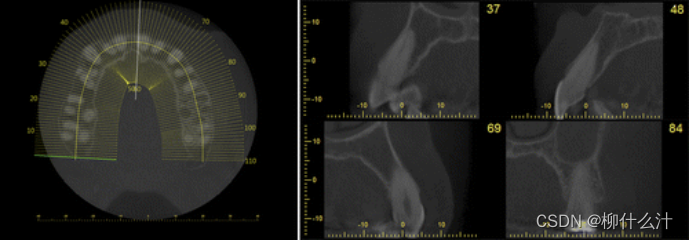

除了合成全景图像外,还可以从垂直于全景曲线的线条中得到截面图像。

左图:横断面图像的位置,垂直于全景曲线,显示在一个轴向切片上。右图:沿曲线不同位置的横断面图像。